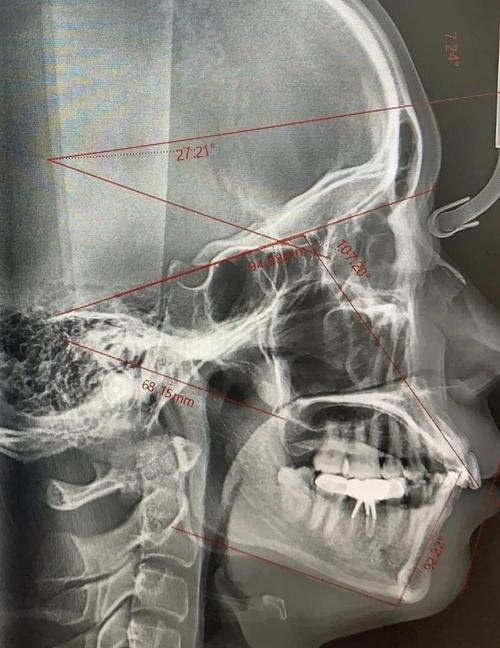

正畸治疗的核心是“移动牙齿”,但牙齿并非孤立存在,其移动方向、距离、速度均需依托周围组织(牙槽骨、牙周膜、颌骨)的生理条件,拍片的作用正是全面评估这些条件:通过全景片(曲面断层片)可观察全口牙齿数量、形态及位置,是否存在多生牙、缺失牙、埋伏牙(如阻生智齿、埋伏尖牙)等异常,部分患者看似牙齿拥挤,实际是因多生牙占据空间导致;若未发现埋伏牙直接开始矫正,可能造成邻牙牙根吸收、囊肿甚至需手术干预,头颅侧位片能精准测量颌骨与牙齿的相对关系,判断是否存在骨性畸形(如上颌前突、下颌后缩、地包天)及畸形程度,这是区分“牙齿问题”与“骨骼问题”的关键——骨性畸形需联合正颌手术,单纯正畸无法解决,若未拍片盲目矫正,可能加重面部畸形,X光片还可评估牙根形态(如牙根是否弯曲、短小)、牙槽骨密度及高度(是否有骨量不足、骨皮质穿孔风险),以及颞下颌关节(TMJ)状态(如髁突位置异常、关节间隙改变),避免因牙齿移动超出生理限度引发关节疼痛、弹响等问题。

| 头颅侧位片 | 颌骨角度、牙齿倾斜度、面部软组织 | 判断骨性畸形类型,设计牙齿移动方向 |